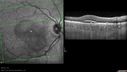

SPECTRALIS-SD-OCT SCAN: The OCT scan of the macula in the right eye does show pigment epithelium thickening, predominately inferior to the fovea where the neovascular complex is with some retinal edema there and subretinal fluid centrally. There is also excrescences off of the pigment epithelium where the white spots are, many of which are under the subretinal fluid, but there is some away from it as well. These appear to indent the small spots which are tiny, roughly 150 microns across, do appear to displace all the layers of the retina, including the external limiting membrane and the other outer lines of the retina and appear to be internal to the basement membrane of the choriocapillaris. It doesn’t appear like there is any choroidal involvement on the OCT scan. The scan of the left eye similarly shows no intraretinal or subretinal fluid. There are however, the deposits which appear to be deep pigment epithelium, but superficial to the basement membrane of the choriocapillaris putting them somewhere in the middle of Bruch’s membrane.